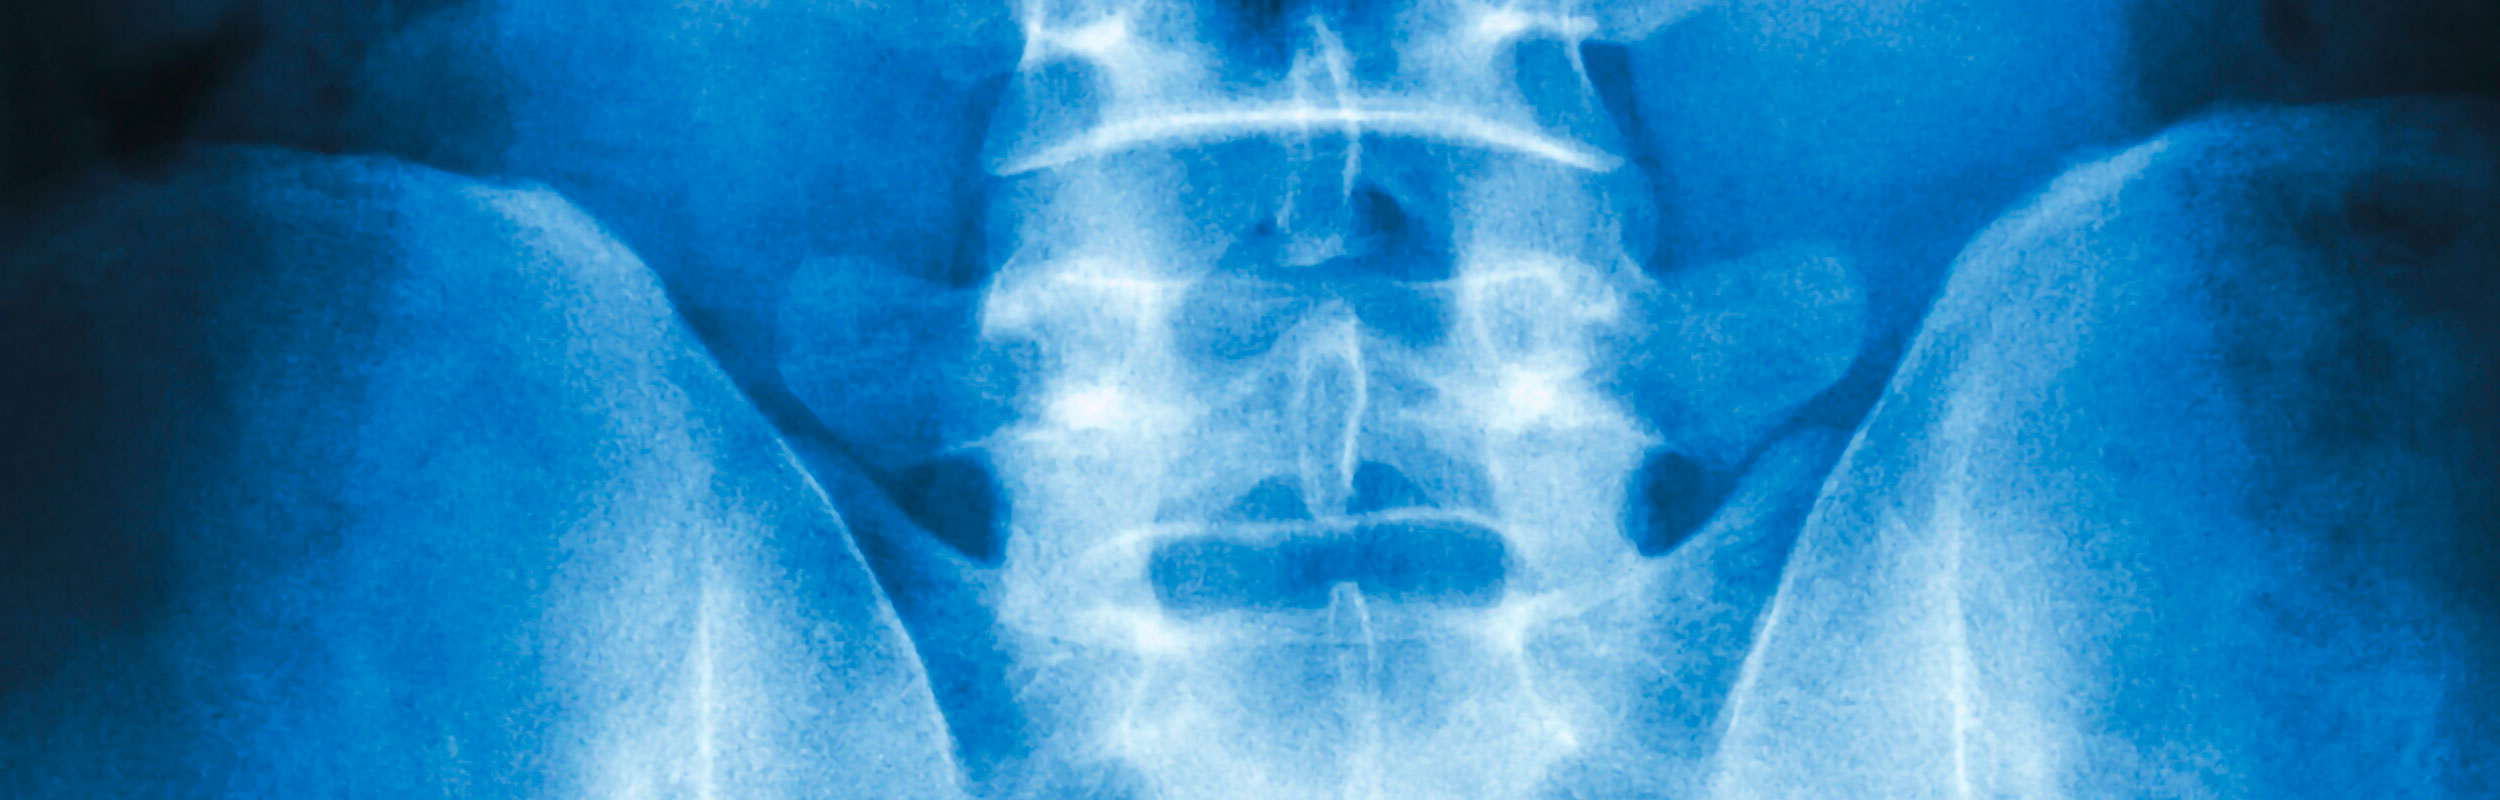

Spezialgebiete und Kernkompetenzen: Wirbelsäule, Endoprothesen und Fuß

Kunstgelenke für Hüft- und Kniegelenk (Endoprothesen)

Das Einsetzen künstlicher Hüft- und Kniegelenke in besonders schonender, minimal-invasiver Technik gehört zu den sehr häufigen Routineoperationen, die ca. 1000 Mal pro Jahr durchgeführt werden. Nach exakter Planung wird das erkrankte Gelenk über einen kleinen Hautschnitt ohne Verletzung von Muskeln entfernt und durch ein Kunstgelenk mit langer Haltbarkeit ersetzt. Die stationäre Aufenthaltsdauer beträgt 5 bis 7 Tage, die Verwendung von Krücken ist nicht unbedingt erforderlich.